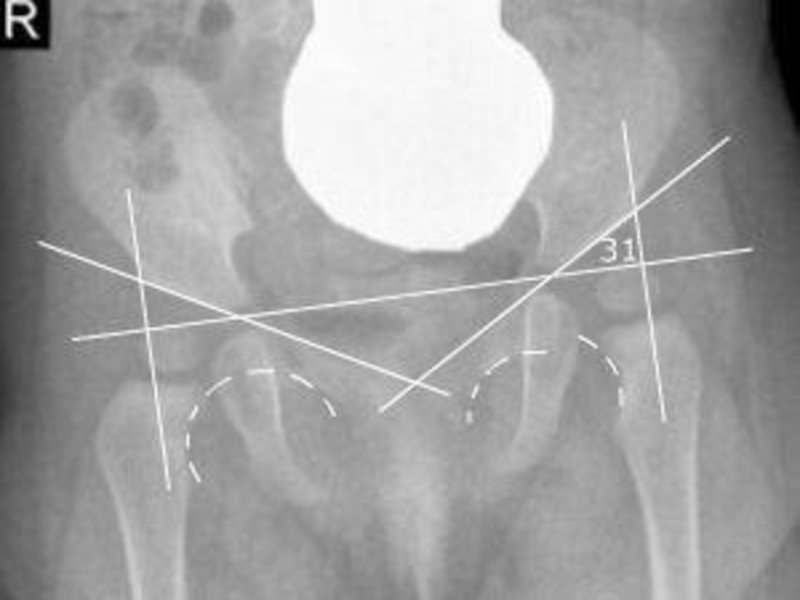

Слайд 201. Определение центрации головки бедренной кости. Проводится продольная ось шейки бедренной

кости (линия ОО1), продолженная в краниальном направлении и касательная к

переднему и заднему краям крыши вертлужной впадины (линия АВ).

В норме продольная ось шейки пересекает касательную на участке протяженностью от середины последней до границы передней и средней ее третей (точки 1 и 2). Отклонение продольной оси кпереди от точки 1 или кзади от точки 2 является признаком передней или задней децентрации.